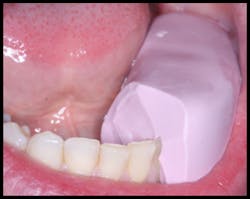

No local anesthetic was administered. Teflon tape was placed onto the adjacent teeth to separate the adjacent teeth and the restoration to create a restoration with interproximal contacts that could be flossed (figure 4).

Figure 4: Teflon tape was placed on the adjacent teeth to create interproximal contacts that could be flossed.